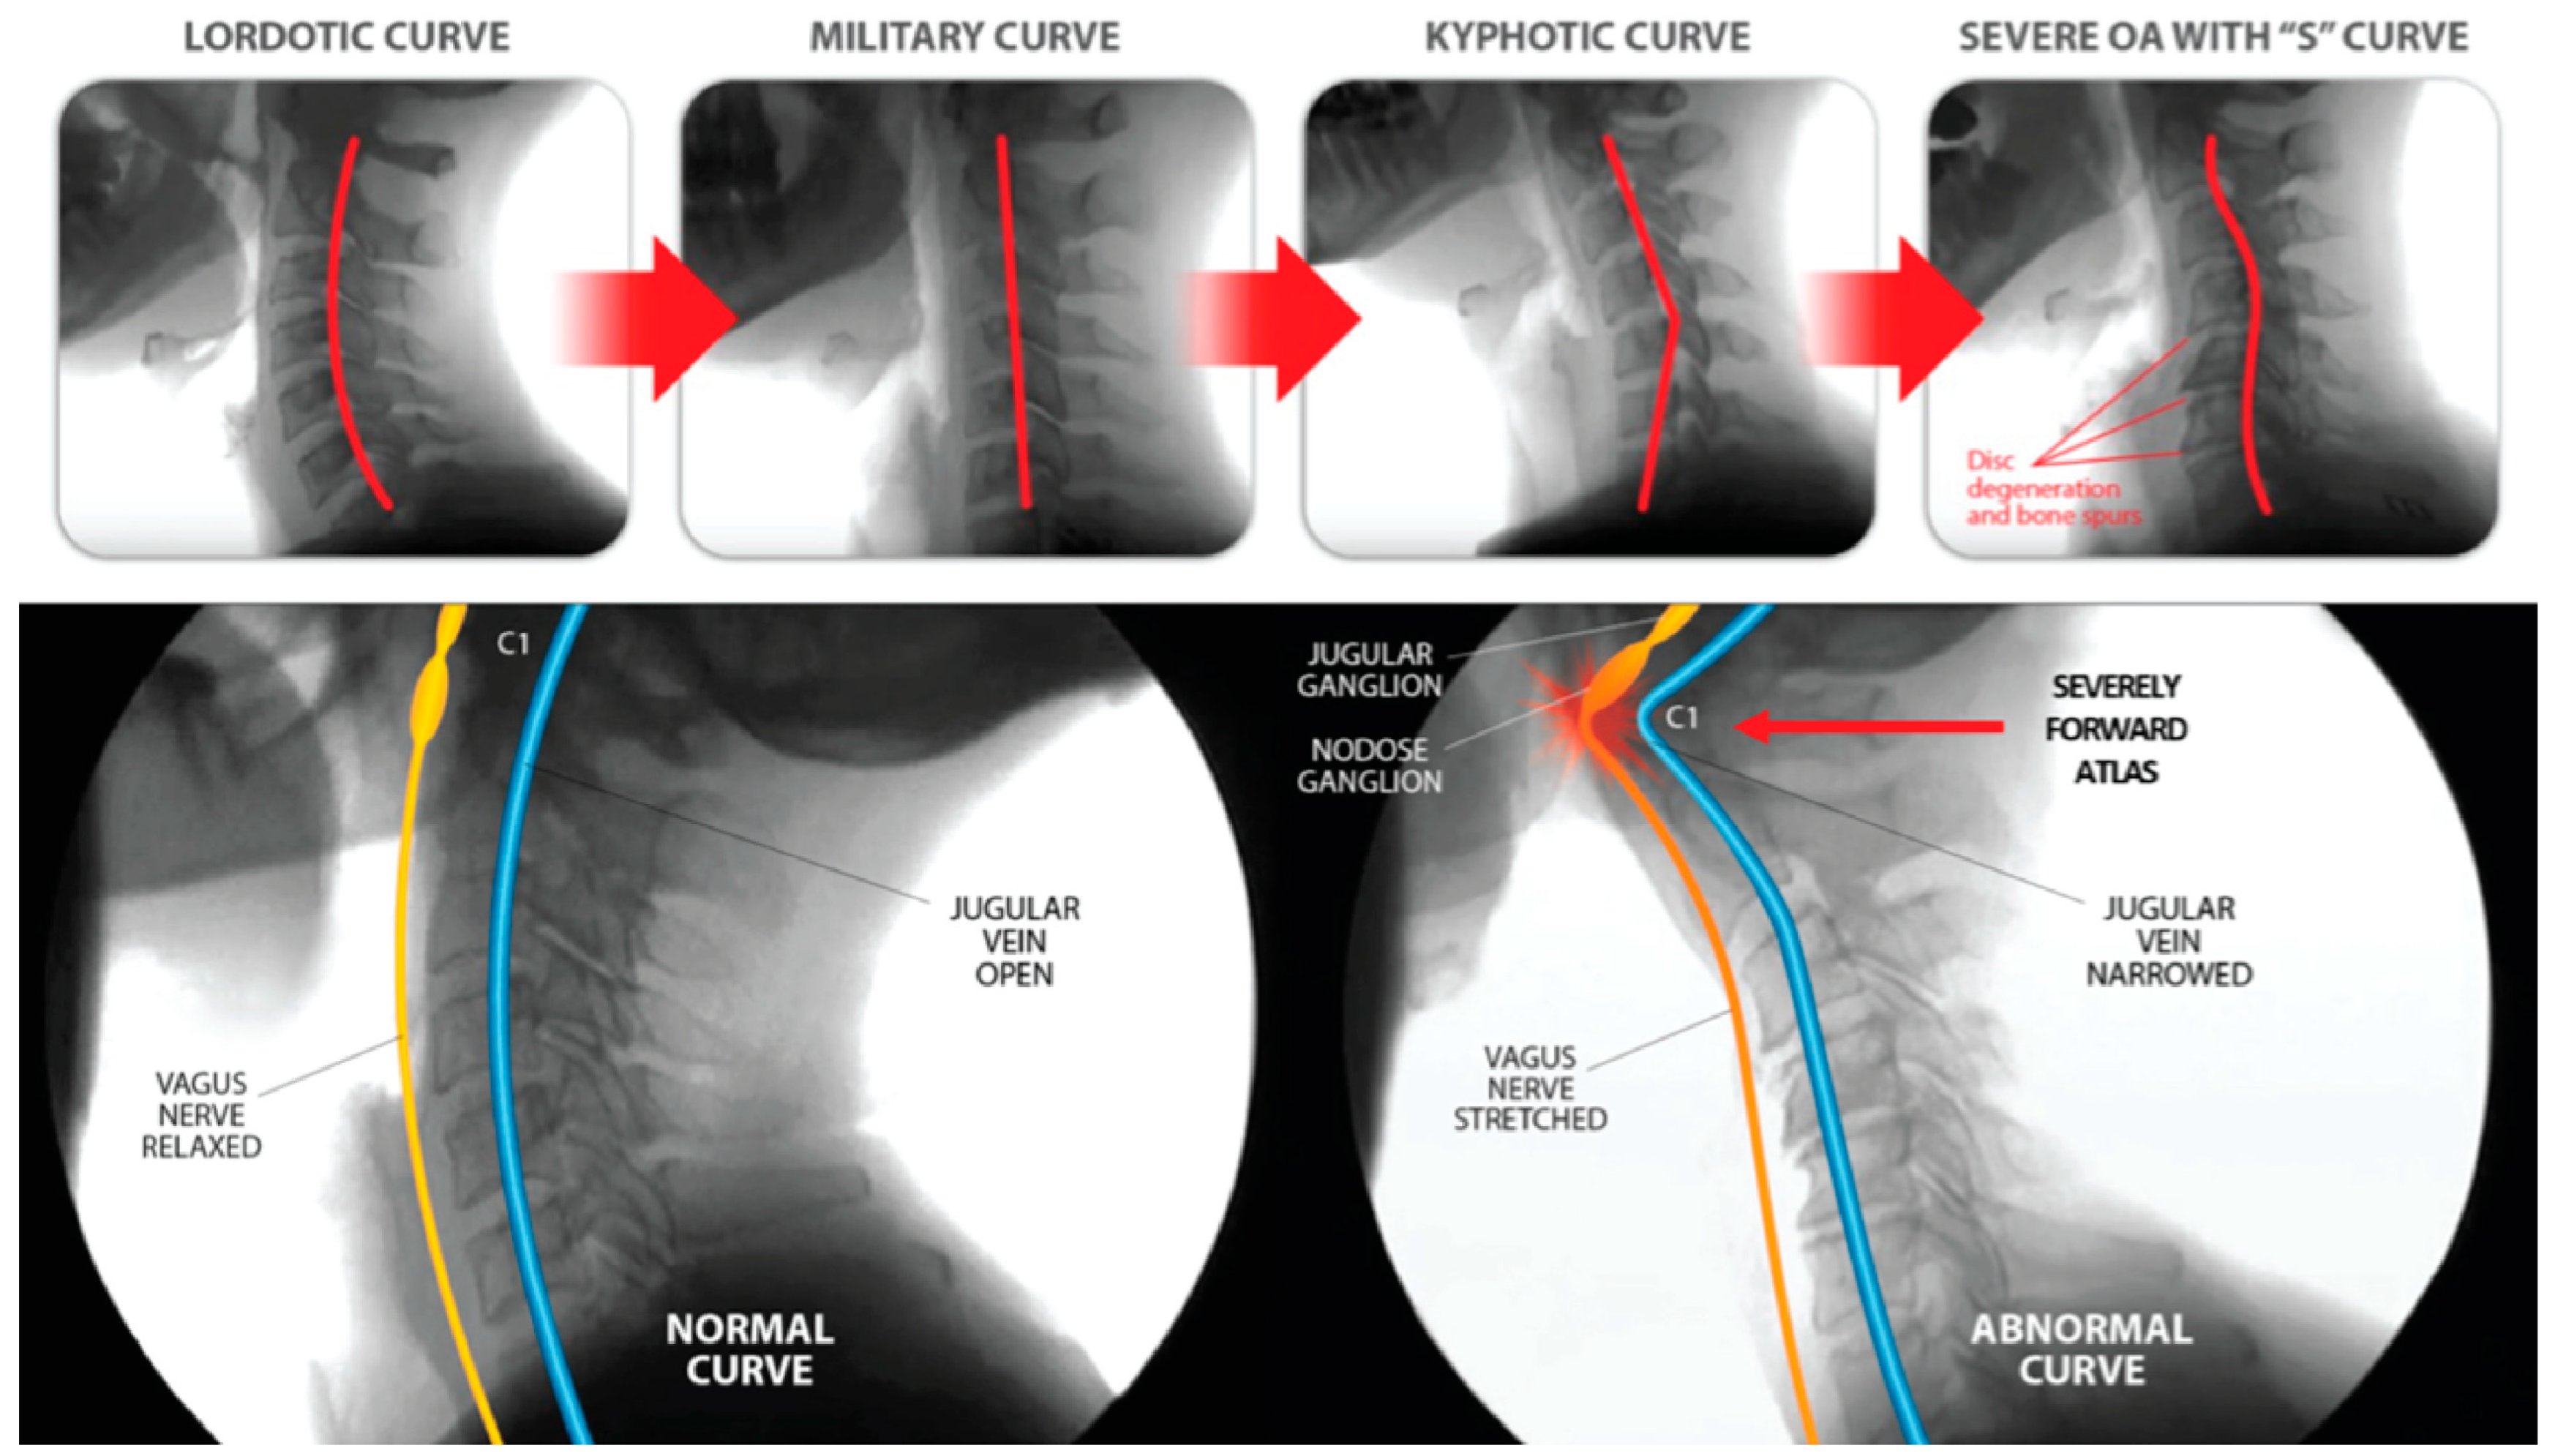

5. Cervical Lordotic Curve

6. Documenting Cervical Structural and Dynamic Carotid Sheath Compression

6.1. Cervical Structural Imaging

6.2. Dynamic Carotid Sheath Compression

7. Internal Jugular Vein Compression